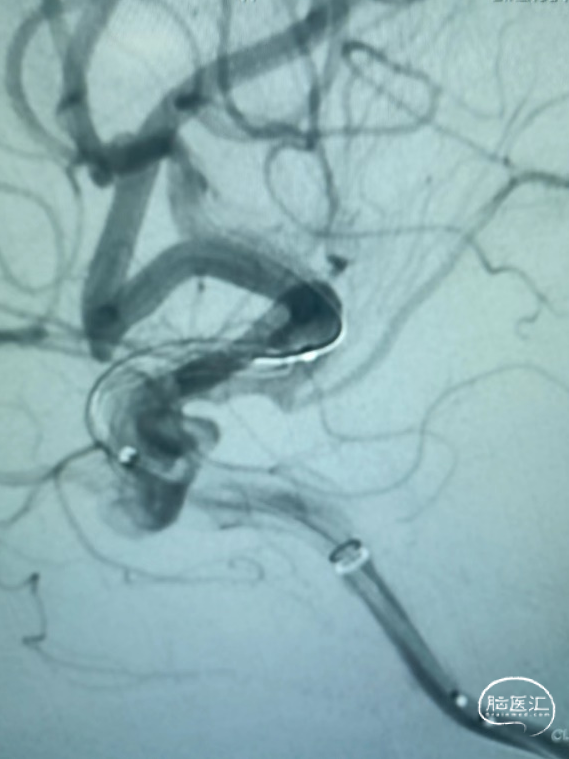

术后正位造影

术后侧位造影

造影剂滞留。

Evolve密网支架输送顺滑,无阻力,到位容易。

支架的径向力强,打开容易,贴壁好。

64根网丝编织,导流效果好,预后佳。